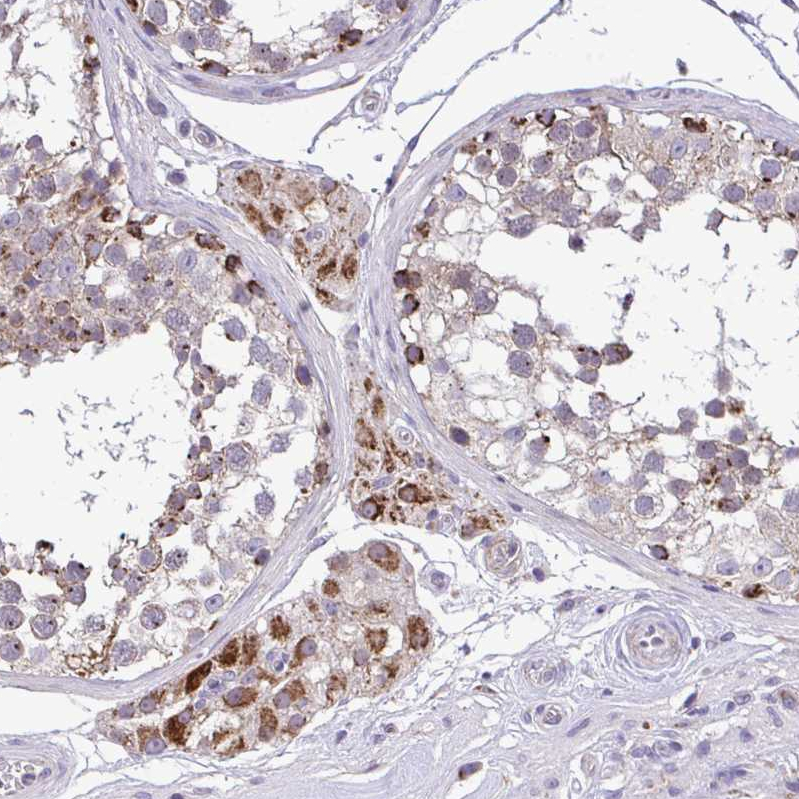

Immunohistochemical staining of human testis shows strong cytoplasmic granular positivity in Leydig cells.